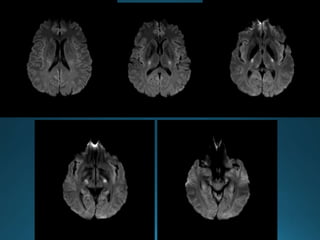

Cerebral Autosomal DominantArteriopathy with Subcortical Infarcts and

Leukoencephalopathy (CADASIL) is characterised by recurrent lacunar and

subcortical white matter ischaemic strokes and vascular dementia in young and

middle age patients without known vascular risk factors

autosomal dominant trait

recurrentTIA and dementia

MRI:

widespread confluent white matter hyperintensities . More circumscribed

hyperintense lesions are also seen in the basal ganglia, thalamus and pons

There is relative sparing of the occipital and orbitofrontal subcortical white matter 2,

subcortical U-fibers and cortex